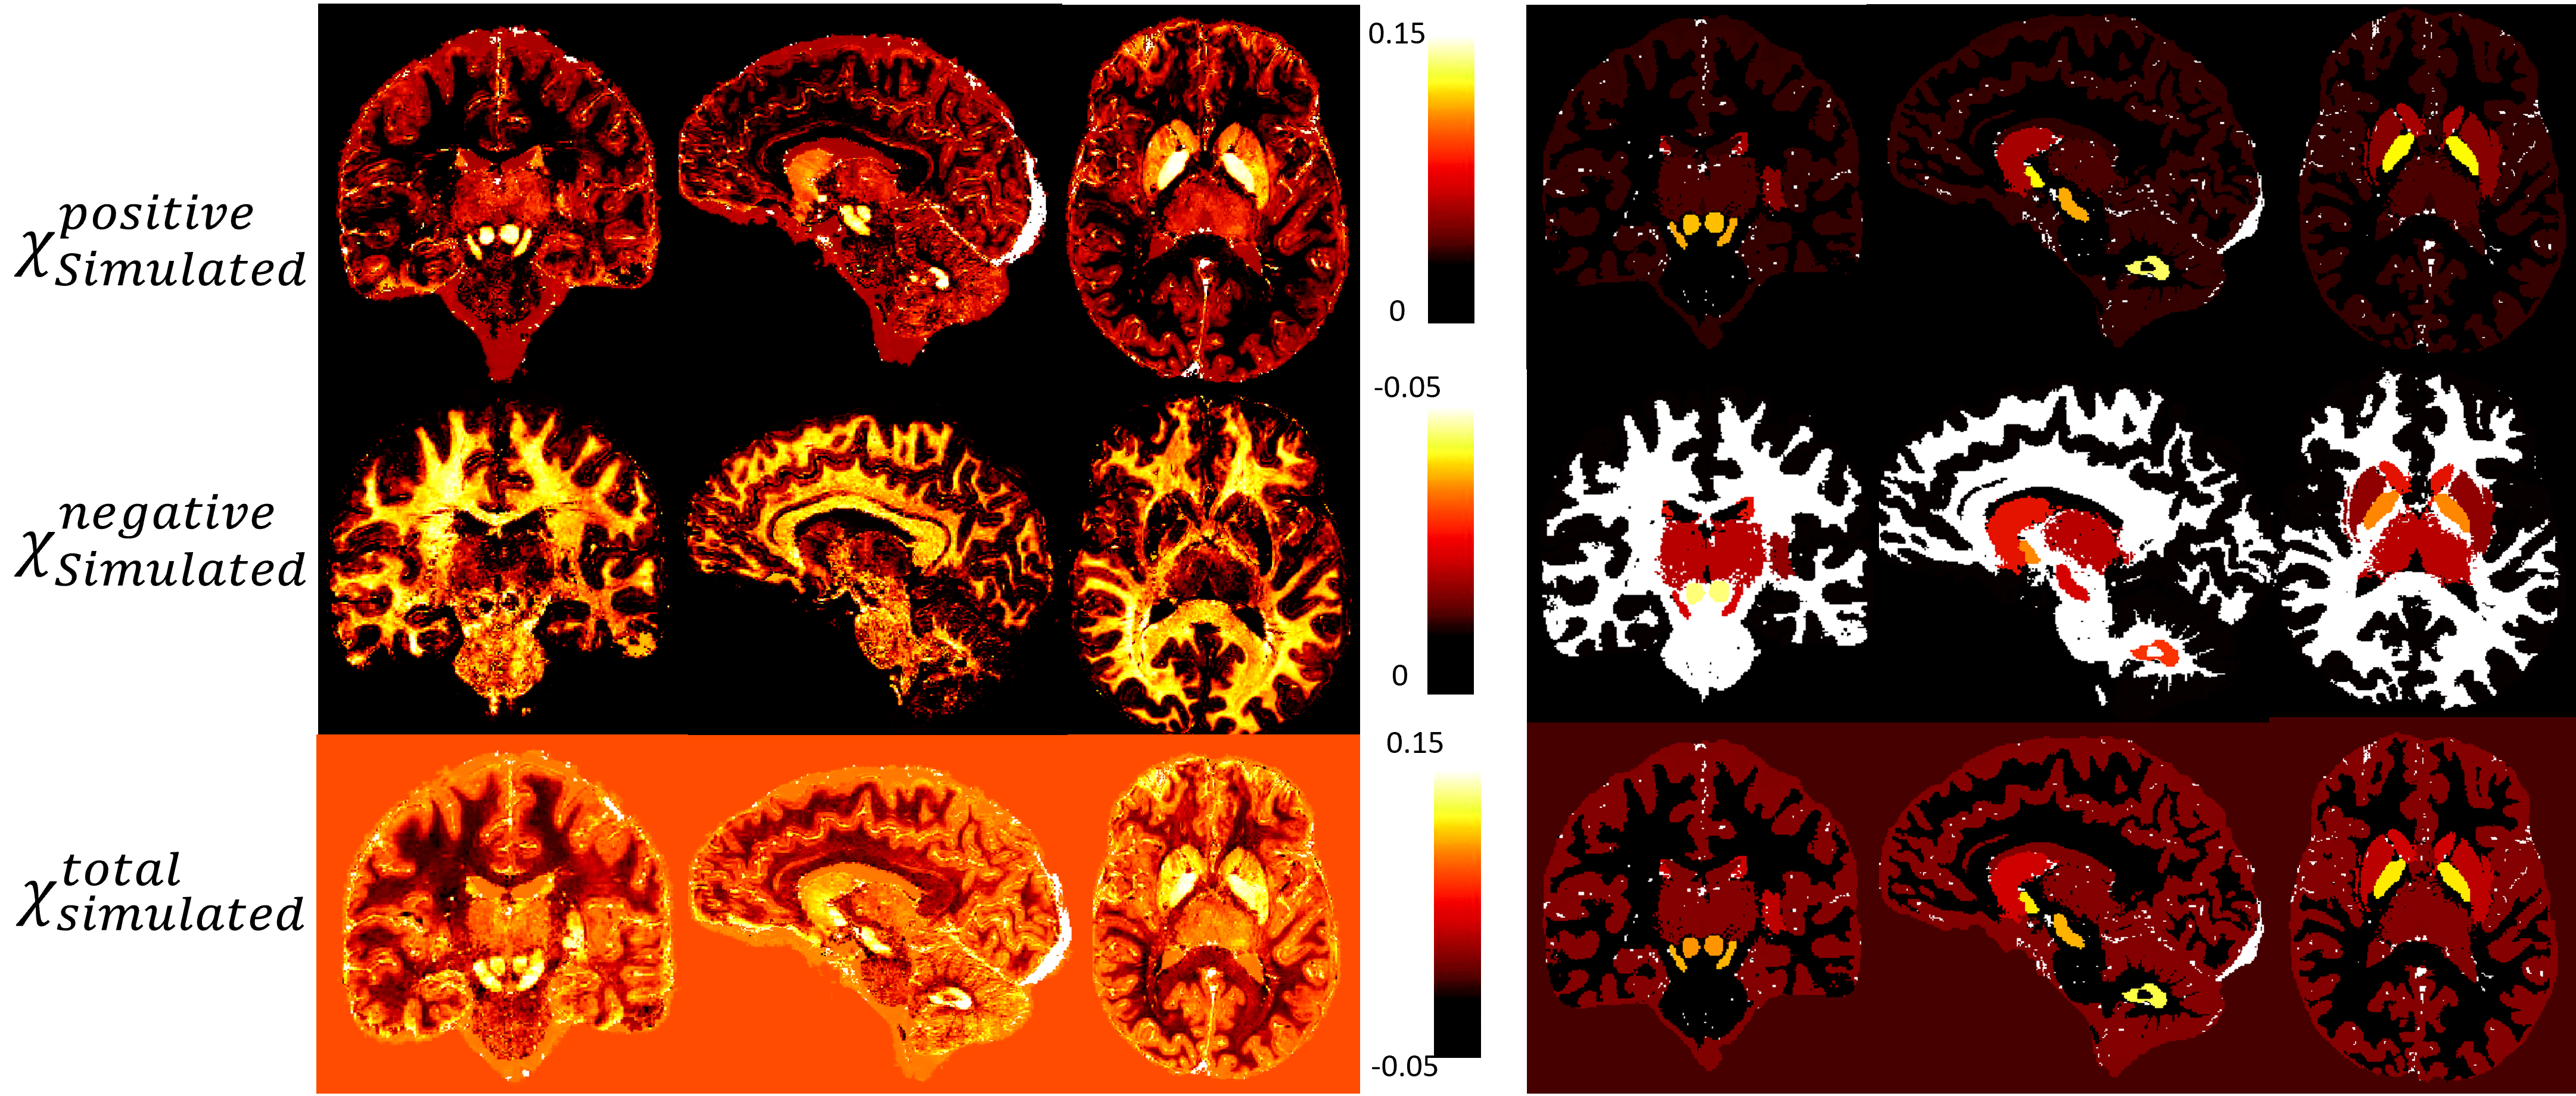

Figure 2: Phantom maps of variable and uniform assessments of brain region values. The left set (a, b, c) illustrates a variable assessment approach, where image a represents χPositiveSimulated, image b represents χNegativeSimulated, and image c represents χTotalSimulated values. The right set (d, e, f) presents a uniform assessment approach, with images d, e, and f mirroring the same representation as a, b, and c, respectively.Figure 2 represents the phantom maps that will be used as ground truth. This figure present two sets of maps: the first (a, b and c) has a variable assessment of brain region values and the second (d, e and f) has a uniform assessment of brain region values. The figure presented in this study exemplifies the comparative analysis of variable and uniform assessments. The findings of these experiments will shed light on the limitations of χ-separation when it comes to the complexity of the used model.